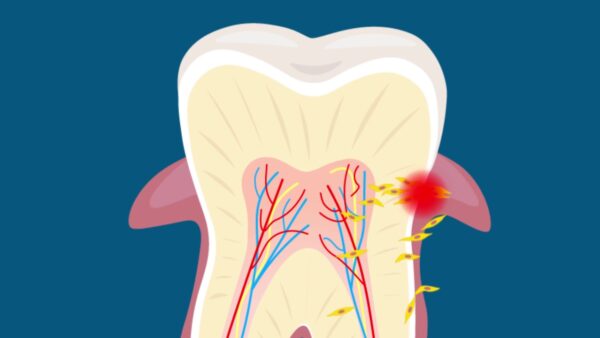

Existe um ditado que diz que nossos dentes são nosso cartão de visita. Em geral, as pessoas costumam ser bem preocupadas com a sua aparência. Ainda mais depois do advento das redes sociais, onde, muitas vezes, a sua imagem é o principal “produto” ali veiculado. Portanto, com o tempo, as pessoas passaram a se preocupar ainda mais com os cuidados pessoais. E na era das selfies, ter um belo sorriso é fundamental.

No entanto, perder um de seus dentes, pode ser algo assustador para qualquer pessoa. Independentemente do quão vaidosa seja essa pessoa. Mas, esse é um problema que muitas pessoas enfrentam. Para termos uma noção, mais de um quarto dos adultos perdem todos os dentes ao chegar aos 74 anos.

Embora os implantes dentários tenham se tornado mais populares e ajudem em relação a isso, eles podem ser realmente desconfortáveis. Especialmente porque eles não se adaptam à boca à medida em que envelhecemos. Porém, uma nova técnica pode ser a esperança das pessoas para cultivar novos dentes em apenas 9 semanas. A técnica consiste no uso de células-tronco do próprio paciente.

Cientistas do Centro Médico da Universidade de Columbia, em Nova York, nos Estados Unidos, desejam conseguir que as células-tronco possam criar um dente anatomicamente correto. O novo dente cresceria no espaço vago na boca da pessoa, se fundindo com o tecido da gengiva circundante.

Tal técnica já se mostrou eficaz no cultivo dos novos dentes, embora ela ainda não tenha sido testada em humanos. Segundo o que foi publicado no Journal of Dental Research, os pesquisadores realizaram experimentos em 22 ratos. Fatores de crescimento foram implantados na boca dos ratos. Logo depois, o novo material ósseo foi regenerado e integrado em apenas 9 semanas. Ainda de acordo com os cientistas, essa foi a primeira vez que estruturas semelhantes aos dentes foram regeneradas em um organismo vivo.

Caso o novo tratamento venha a ser aprovado em humanos, uma série de benefícios virá acompanhada a ele. Como o dente é cultivado no espaço onde ele irá crescer, não há a necessidade de se colher células-tronco externas ou criar um ambiente externo para o seu cultivo, à medida que ele cresce.

Dessa forma, os pesquisadores acreditam que essa será uma solução mais econômica para aqueles que não podem pagar por implantes dentários. Sem contar que, como eles crescem diretamente no lugar certo e na própria boca do paciente, é bem provável que a recuperação seja mais rápida e as probabilidades de problemas futuros sejam minimizadas.

Os implantes dentários, por enquanto, ainda são a alternativa mais próxima de substituição dos dentes perdidos em humanos. Porém, os implantes podem ser dolorosos e exigem um longo processo de cicatrização. Outro ponto negativo é que, com uma certa frequência, eles não se adaptam à boca das pessoas conforme elas envelhecem. O que pode acabar se tornando um grande problema.

O que nos resta agora é torcer para que esse novo tratamento se torne uma realidade muito em breve. Desde já, a Universidade de Columbia registrou patentes para essa nova tecnologia e tem buscado formas para tornar o processo comercialmente viável.